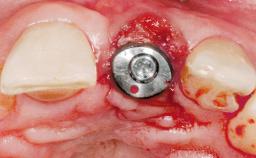

Immediate Placement of an Implant in a Maxillary Left Central Incisor Site

Type of Implants One-Piece

Attachment One-Piece

Placement Protocol Immediate implant placement

Tooth Site Maxillary incisor or canine

Provisional Implant-Supported Prosthesis Prosthodontic margin > 3 mm apical to mucosal margin Prosthodontic margin > 3 mm apical to mucosal margin